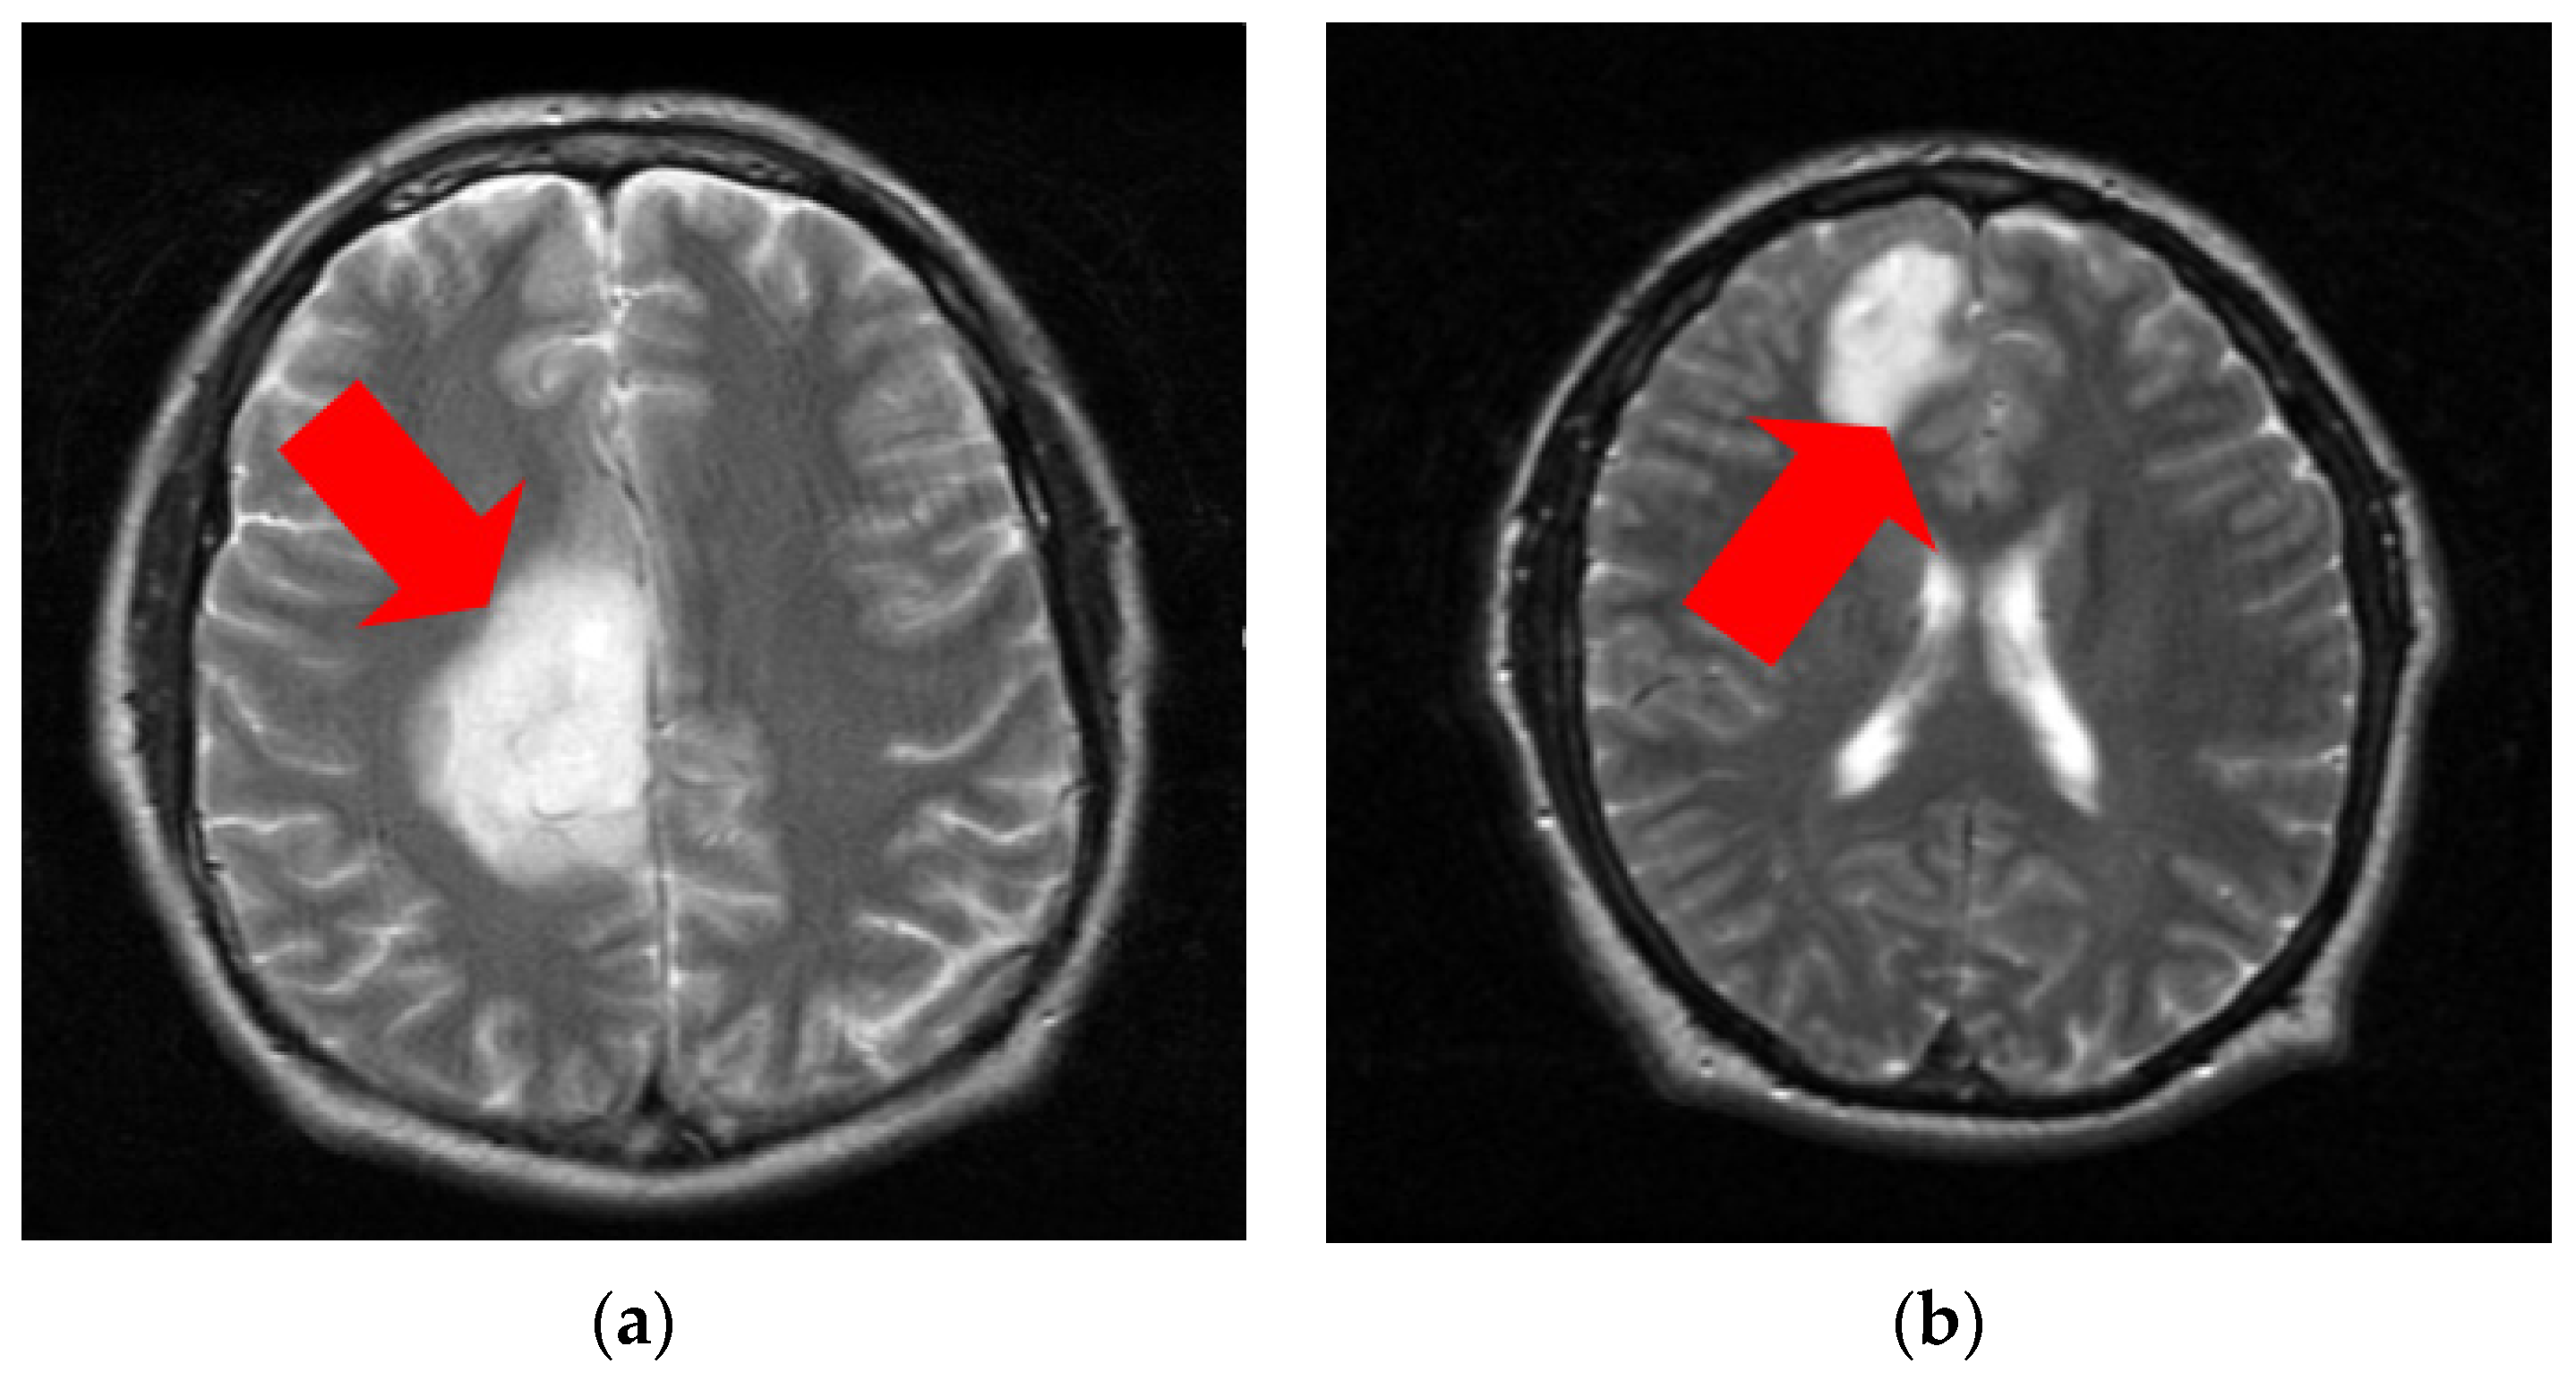

3.1. Dataset

3.2. GrowCut Segmentation